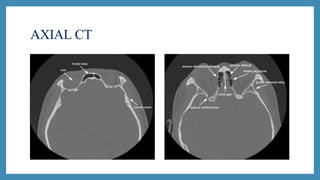

CT scan

 CT scans: Excellent views of the sinuses, best for osteomeatal

complex and ethmoidal disease

 “Limited CT Evaluation” – slice 3-4 mm

 CT navigation:

 A computer is used to identify the 3- dimensional location of a

probe tip placed within the patient's nose or sinuses..

 Improves anatomical identification and avoid damage to vital

neighbouring structures such as the brain and eyes.

AXIAL CT

CT scan  CTscans: Excellent views of the sinuses, best for osteomeatal complex and ethmoidal disease  “Limited CT Evaluation” – slice 3-4 mm  CT navigation:  A computer is used to identify the 3- dimensional location of a probe tip placed within the patient's nose or sinuses..  Improves anatomical identification and avoid damage to vital neighbouring structures such as the brain and eyes.